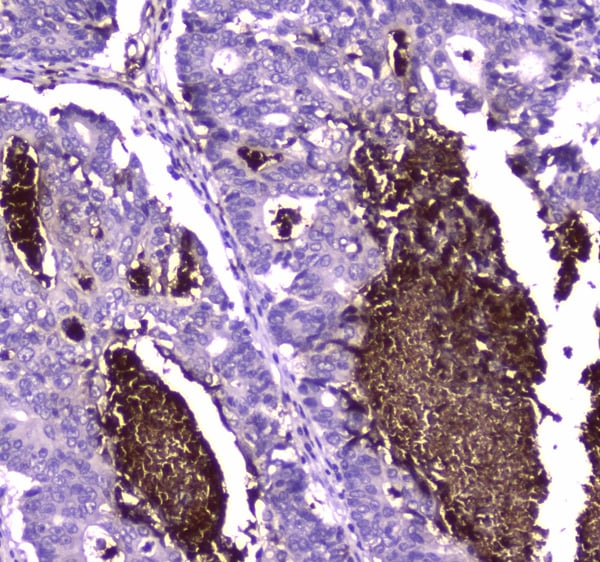

(Figure 2. IHC analysis of Lactoferrin using anti-Lactoferrin antibody (AAA124585).Lactoferrin was detected in paraffin-embedded section of human intestinal cancer tissue. Heat mediated antigen retrieval was performed in citrate buffer (pH6, epitope retrieval solution) for 20 mins. The tissue section was blocked with 10% goat serum. The tissue section was then incubated with 2ug/ml rabbit anti-Lactoferrin Antibody (AAA124585) overnight at 4 degree C. Biotinylated goat anti-rabbit IgG was used as secondary antibody and incubated for 30 minutes at 37 degree C. The tissue section was developed using Strepavidin-Biotin-Complex (SABC) with DAB as the chromogen.)

IHC (Immunohiostchemistry)